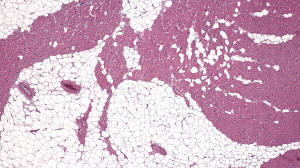

Figure C. H&E x4

Histology: H&E staining (Figures C-F) from the explanted heart shows patchy replacement of the myocardium by adipose tissue.